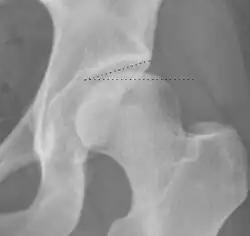

| Tönnis angle |

|

Slope of the sourcil (the sclerotic weight-bearing portion of the acetabulum) | 0 to 10°